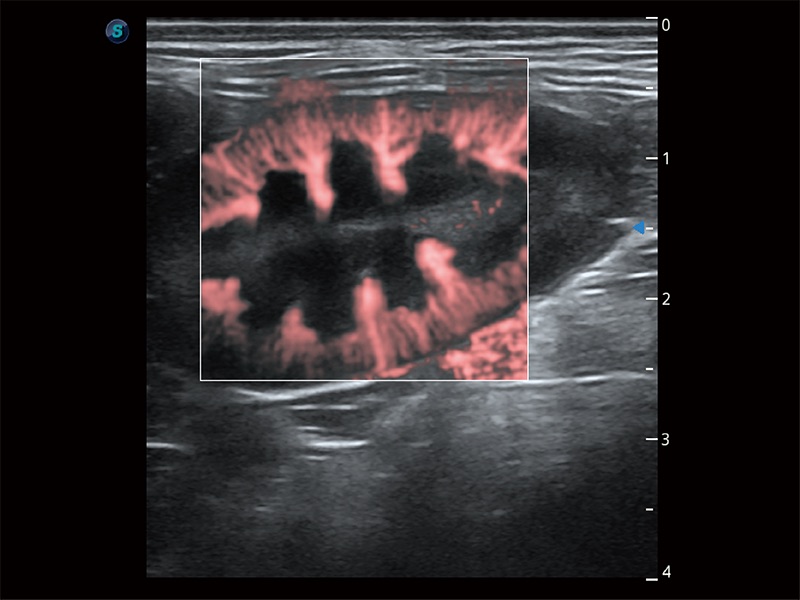

操作简便,无需高频度外力作用即可真实反映组织的形变,快速评估肿瘤良恶性。